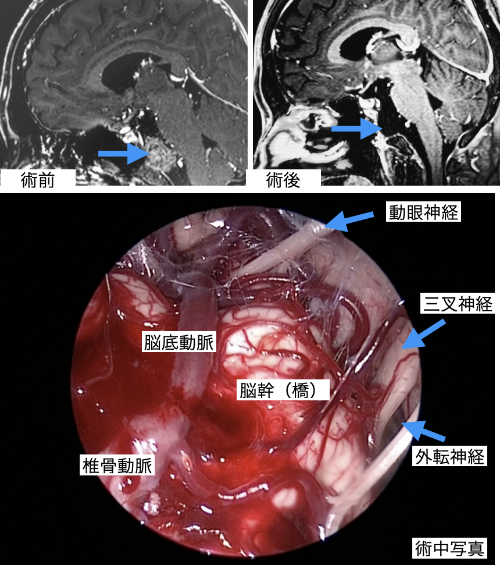

内視鏡システム | エム・シー・メディカル株式会社。脊椎内視鏡手術|平井整形外科クリニック|横浜市港北区綱島の。脊椎内視鏡センター|脊椎脊髄末梢神経外科|新百合ヶ丘総合病院。内視鏡手術の基礎から応用までを網羅した実用書。神経内視鏡手術 | 藤田医科大学 医学部 脳神経外科学講座。- タイトル: スタンダード 内視鏡手術- 出版社: MEDICAL VIEW1度も読んでいない新品ですが素人の自宅保管になりますので、完璧な新品を求めている方は落札をご遠慮下さい。裁断済み‼️スキャナーが必要です‼️皮膚科の処方ノート 2023。他にも多数出品しておりますので是非宜しくお願い致します。4冊セット 標準理学療法学。自己紹介文を必ず読んでから購入お願い致します。【裁断済み】 内科学 第12版 全6巻セット 朝倉書店。